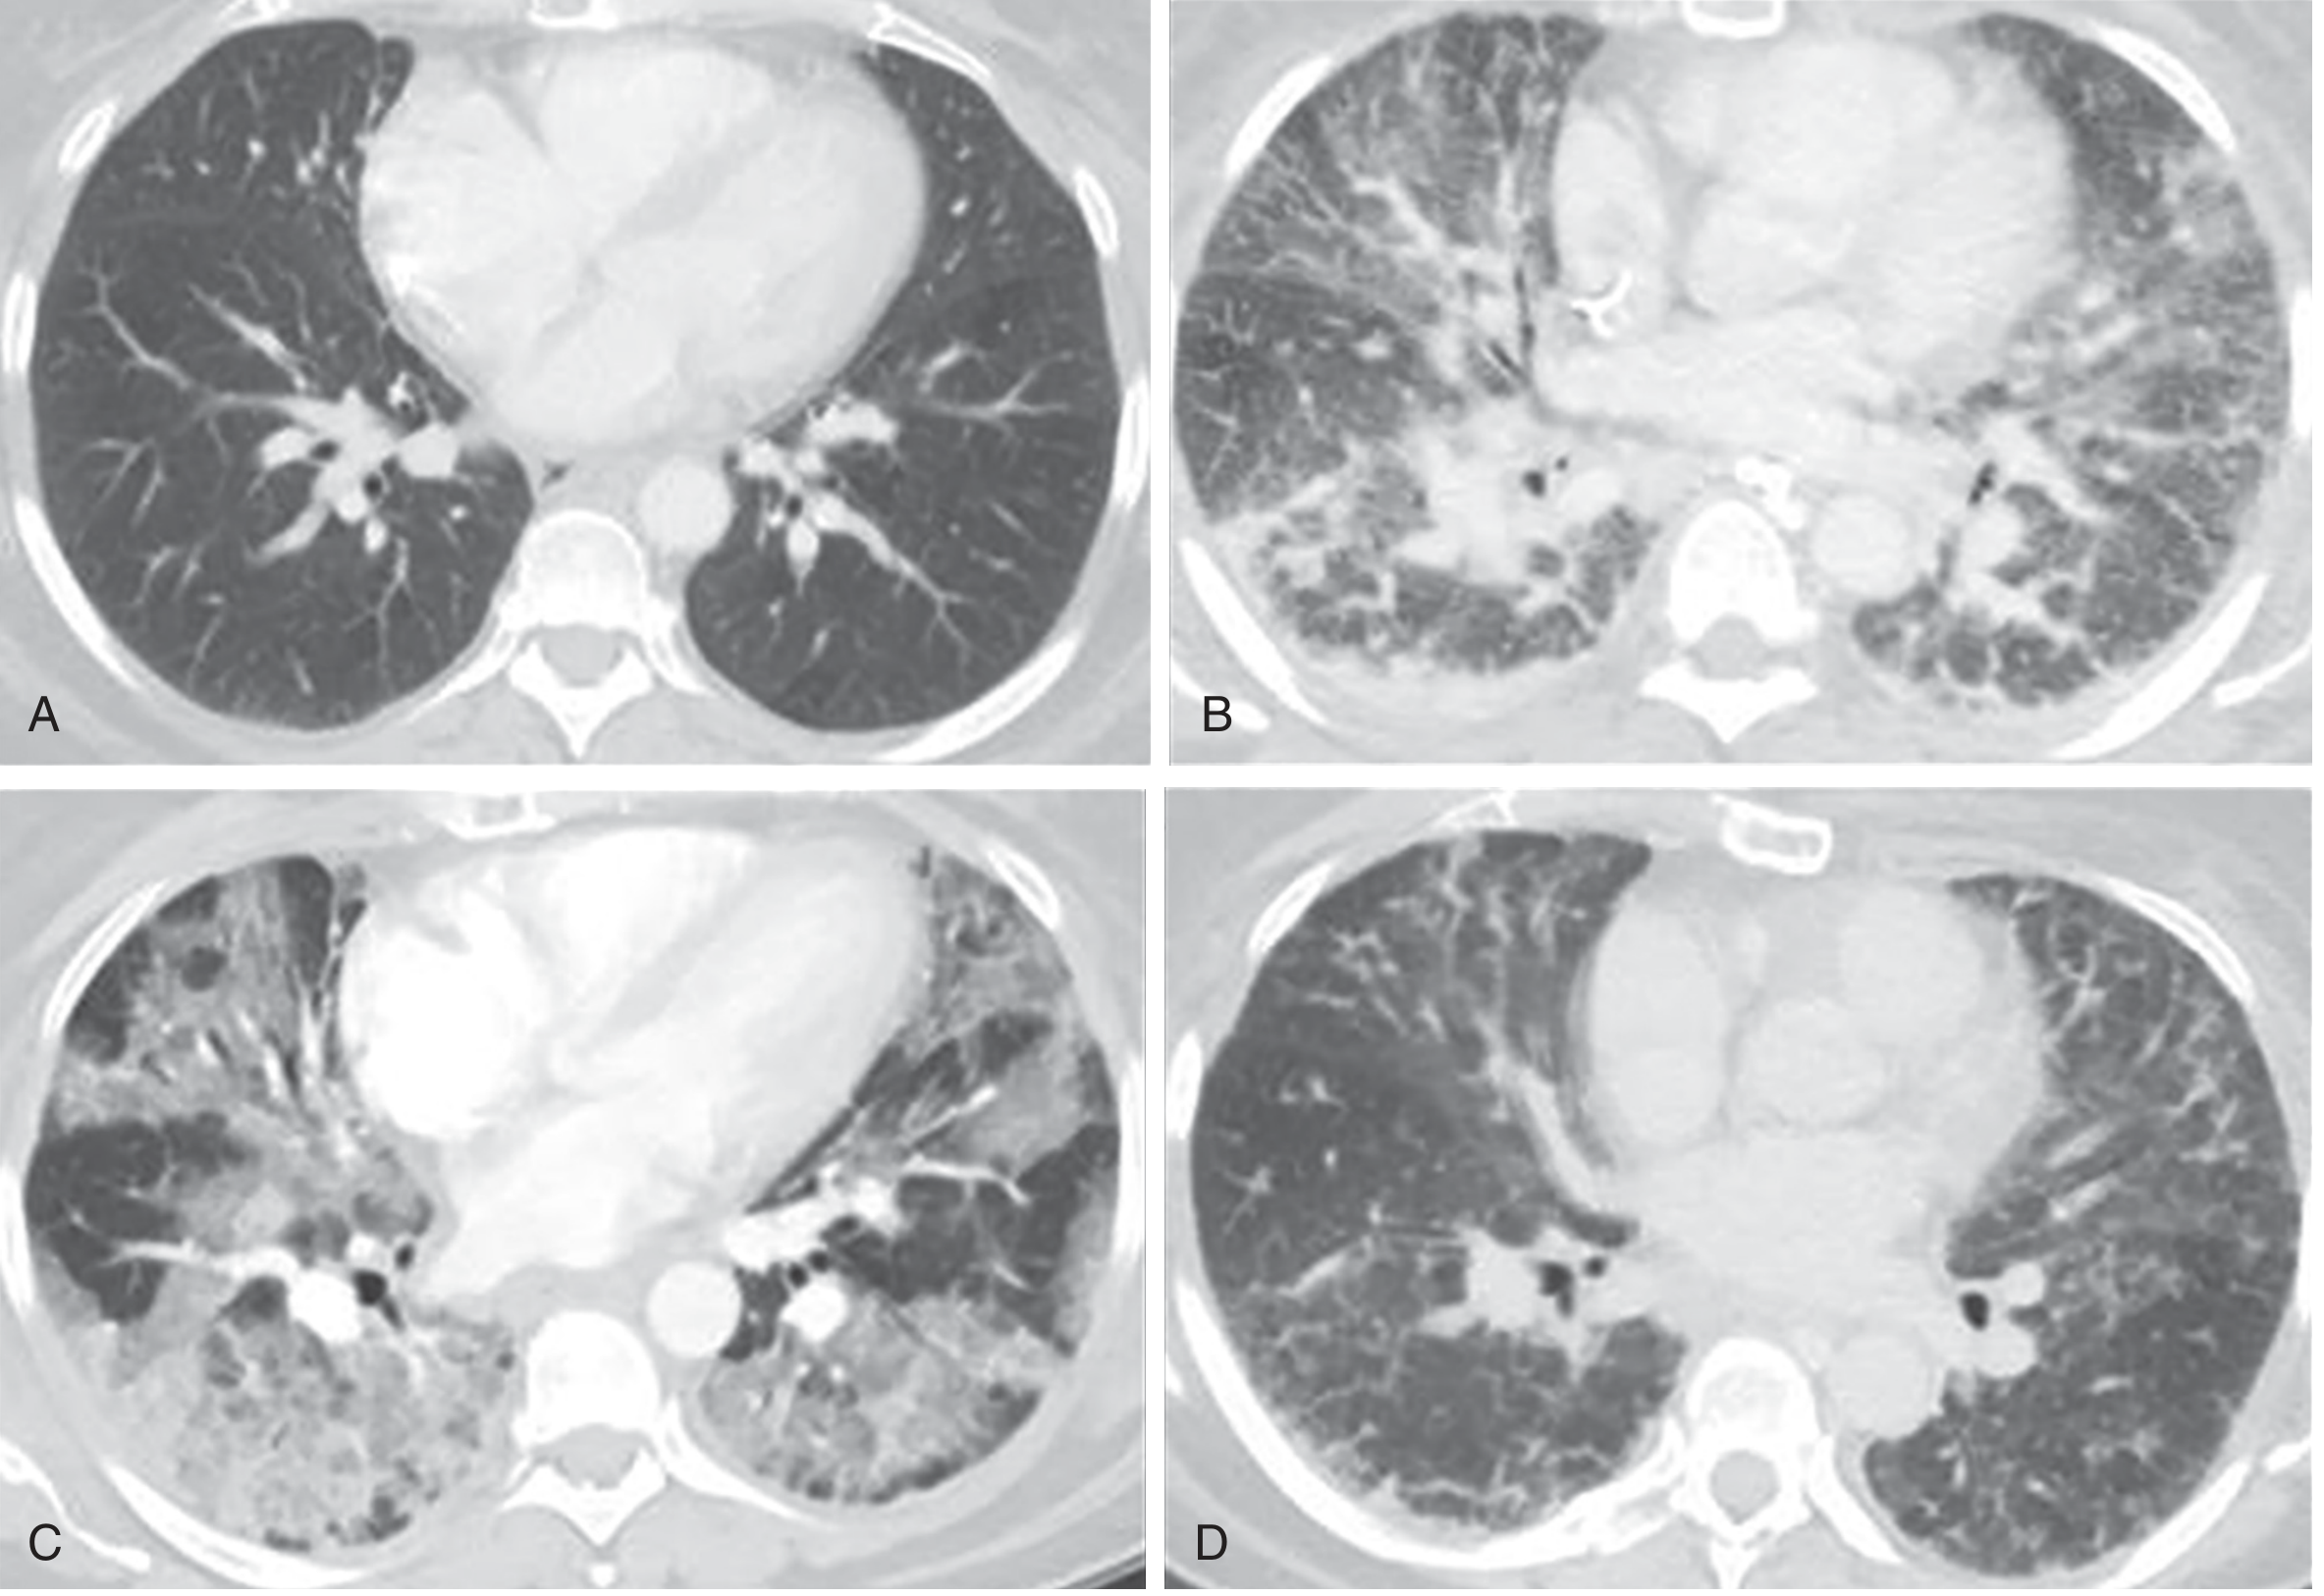

CT scan showing the three phases of ARDS — A: baseline, B: exudative phase with bilateral ground-glass opacities, C: proliferative phase with architectural distortion, D: fibrotic phase with linear/reticular changes

Figure 134.2 — CT demonstration of ARDS phases. B: Exudative phase; C: Proliferative phase; D: Fibrotic phase. — Murray & Nadel's Textbook of Respiratory Medicine

PhaseTimingPathology

ExudativeDays 1–7Hyaline membranes (cellular debris + proteins + surfactant), protein-rich alveolar fluid, neutrophilic infiltrate, widespread epithelial disruption

ProliferativeDays 7–21Reorganization of hyaline membranes, early fibrosis, obliteration of pulmonary capillaries, decreased neutrophils

Fibrotic>2 weeks (subset)Pulmonary fibrosis; fibroproliferation may begin as early as 24 hours after onset (elevated N-terminal procollagen III in BAL fluid)

Importantly, only ~50% of ARDS patients show DAD on biopsy or autopsy. Those with confirmed DAD are younger, more severely ill, have worse compliance and oxygenation, and are five times more likely to die of hypoxemic respiratory failure.